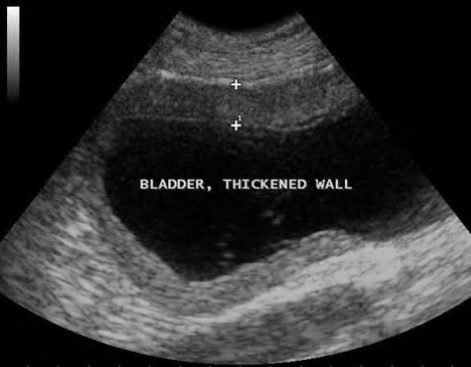

Urinary bladder

bladder wall should be smooth and uniform

routinely used to collect urine sample via cystocentesis

Function:

- collect, store, and release urine